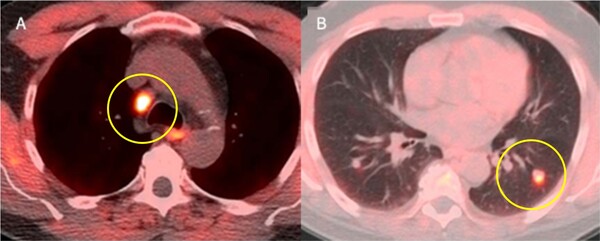

암세포가 정상세포에 비해 포도당을 더 많이 이용한다는 성질을 활용해 포도당과 방사성동위원소를 결합해 체내에 주사해 암세포 주변에 방사성동위원소가 집중적으로 달라붙어 에너지를 방출하도록 하는 것이다. 이때 PET-CT로 확인하면 암이 생긴 부위를 실시간 영상으로 볼 수 있다.

뿐만 아니라, 림프절 등 전신으로 전이되는 재발 암 진단에 효과적으로 활용된다. 방사성의약품은 질병에 따른 생화학적 변화를 세포나 분자 단위로 세밀하게 보여주는 특징이 있기 때문에 아직 크기가 작거나 일반적인 영상 진단으로 확인이 어려운 부위, 발병 초기의 암도 비교적 정확하게 확인할 수 있다.

예를 들어 전립선암은 재발 시 림프절을 통해 전신과 뼈로 전이되기 쉬운 특징을 가지고 있는데, 방사성의약품을 활용하면 환자의 불편을 덜어 주면서 정확도 높게 암의 재발과 전이 여부를 판별할 수 있다.

암 진단 방사성의약품은 전신 암을 진단하는 ‘FDG’, 전립선암의 재발·전이를 진단하는 ‘FACBC’ 등이 있다. 특히 듀켐바이오를 통해 국내 공급되기 시작한 ‘FACBC(제품명:18F 플루시클로빈)’는 재발 또는 전이가 의심되는 전립선암 환자를 대상으로 한 진단용 방사성의약품으로 이미 미국과 유럽 시장에서는 널리 사용되면서 유효성이 입증된 바 있다.